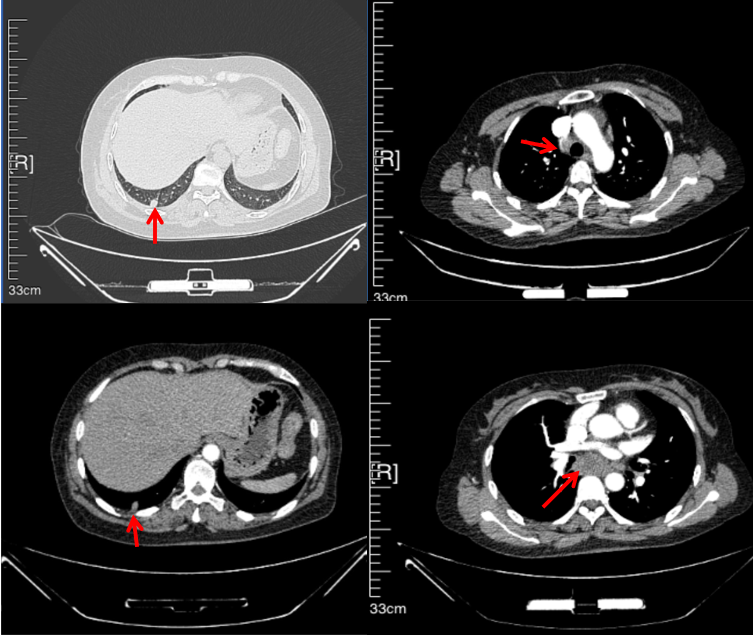

56岁,女性,无吸烟史饮酒史,既往体健。2023年02月患者体检发现肺占位性病变,胸部增强CT:右肺下叶后基底段结节;右侧锁骨上及纵隔内多发淋巴结肿大。PET-CT:右肺下叶周围型肺癌可能性大;1R、2L、3P、4R、4L及7组淋巴结转移可能性大。2023年02月就诊于本院胸外科行超声胃镜下纵隔肿物穿刺活检术,病理:结合免疫组化,符合肺腺癌。行NGS基因检测:EML4:exon20-ALK:exon20融合。PD-L1(克隆号22C3)TPS=55%。

治疗经过:2023年3月27日始行恩沙替尼靶向治疗至今,最佳疗效为PR,末次评效为维持PR。期间出现轻度肝功能异常(DILI 1级),对症处理后好转。截止目前PFS为26个月。

2023年2月20日基线检查

2024年6月复查PR(最佳疗效)

2024年12月复查维持PR

2025年3月复查维持PR